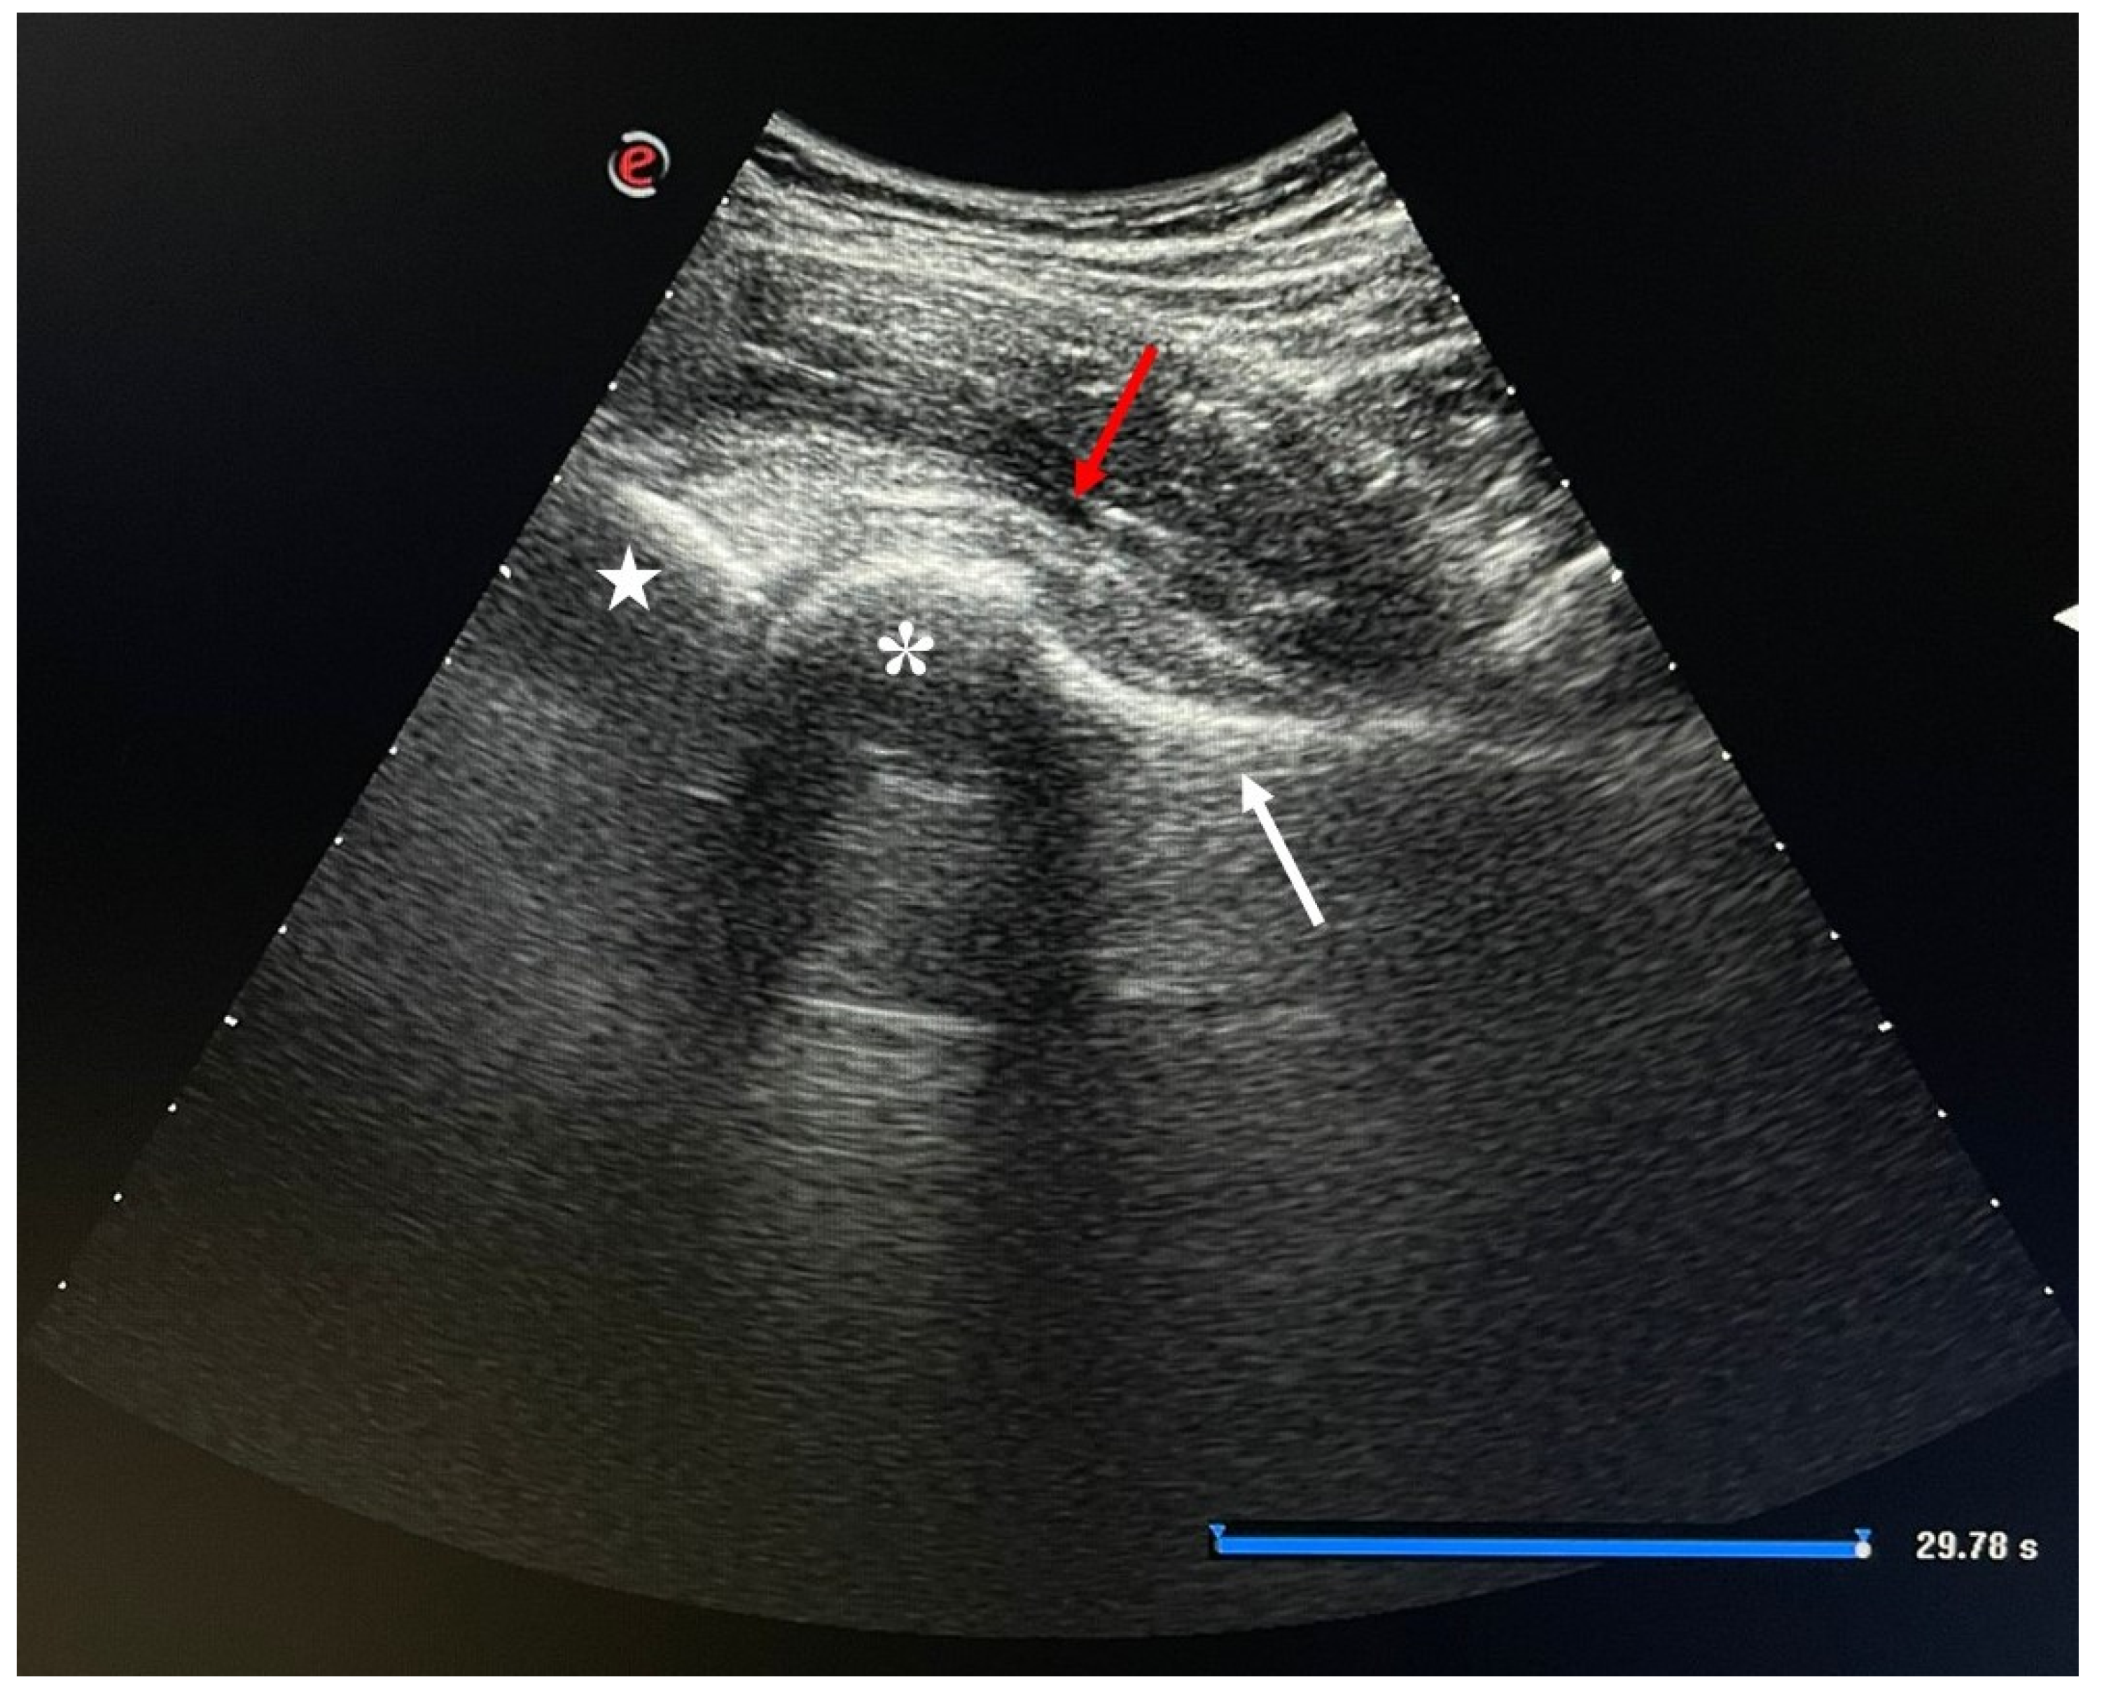

4.1.2. Injection Procedure